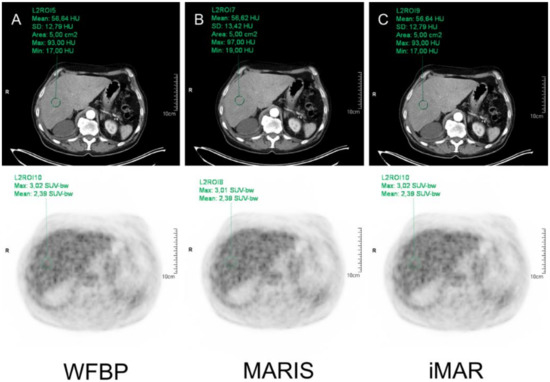

CT Images using WFBP, MARIS, and iMAR-hip as algorithms were investigated for HU analysis. For SUV analysis, PET images based on the three CT reconstructions were used. In WFBP reconstruction, a circular region of interest (ROI) was placed in the respective organ and was automatically copied to MARIS and iMAR-hip reconstruction as well as to all three PET reconstructions (Figure 1).

Figure 1.

Example of HU and SUV measurement in the liver in WFBP (A), MARIS (B), and iMAR (C).